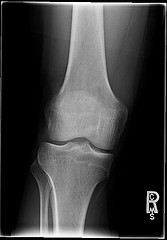

Knee pain from osteoarthritis studied

Researchers from Wake Forest University, led by Dr. Stephen Messier, enrolled 454 elderly adults with significant knee pain resulting from osteoarthritis. They were over 55 years old, lived in an elderly community, and all were obese or overweight, with BMIs ranging from 27 to 41.

The researchers divided the patients into three groups. For 18 months, one group exercised, and another group was given an intensive weight loss diet plan. The third group was given the intensive weight loss diet plus exercise.